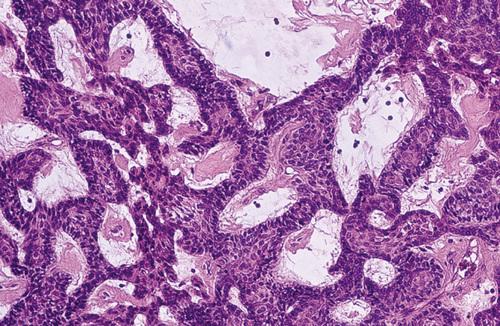

Histopathologic Features

- islands of epithelium in a fibrous connective tissue stroma with ameloblast-like cells with reversed polarity (follicular type)

Multiple islands of odontogenic epithelium demonstrating peripheral columnar differentiation with reverse polarization. The central zones resemble stellate reticulum and exhibit foci of cystic degeneration.

ameloblastoma, follicular pattern